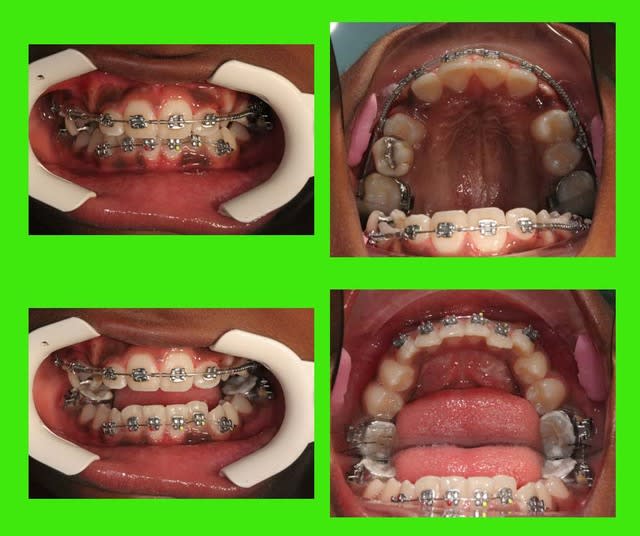

si ce n’était pas moi qui présentait ce cas (10 ans)

vous penseriez extractions ou pas d’extraction

P.S. : désolé, la photo en bas à droite est inversée

Photos du cas

voici les photos du m jour

bouche fermée

bouche ouverte

arcades

@+ Bjc.